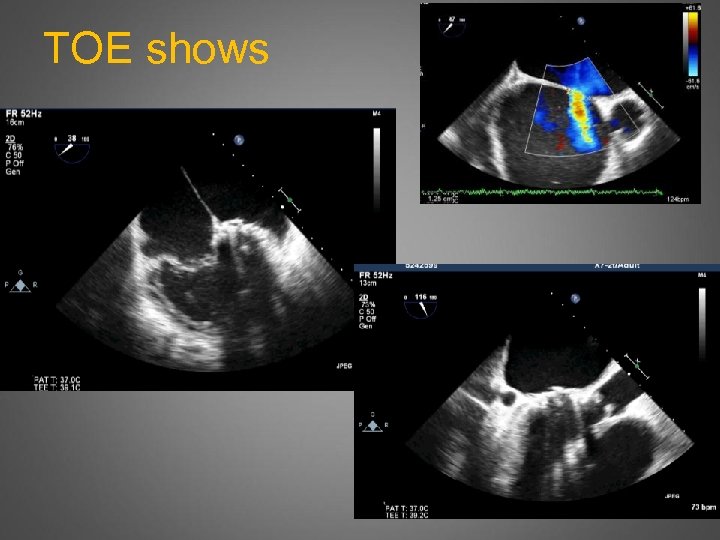

TOE shows

Redo MV, AVR, TVR, ASD. Inotropes, CVP 23, BP 93 still pre-bypass